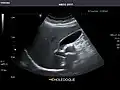

Abdominal Ultrasound (Full Exam)

STRUCTURED REPORT

(Technique: Transabdominal ultrasonography; Device: Toshiba Aplio XG)

Liver: Diffusely homogeneous and normal in echogenicity. No focal mass or contour nodularity. No intrahepatic biliary ductal dilatation.

Portal Vein: Patent main portal vein.

Gallbladder: No stones, wall thickening, or pericholecystic fluid.

Common Bile Duct: Nondilated measuring 1.3 mm at the level of the porta hepatis.

Pancreas: Visualized portions unremarkable.

Spleen: Normal in size.

Kidneys: Right and left kidneys measure 11.5 cm and 12 cm in length respectively. No hydronephrosis. Small left lower pole kidney cyst.

Ascites: None.

Aorta: Visualized portions normal in caliber, 16 x 15 mm.

IVC: Normal.

IMPRESSION:

Normal abdominal ultrasound.